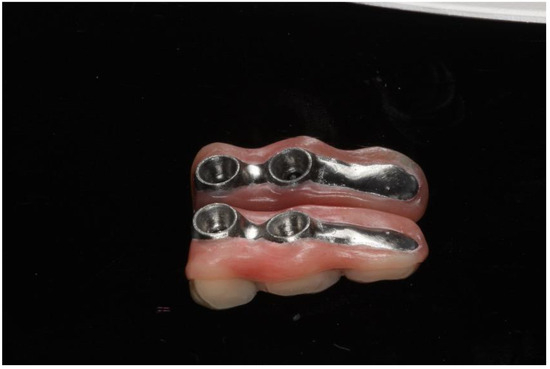

2.1. Case 1